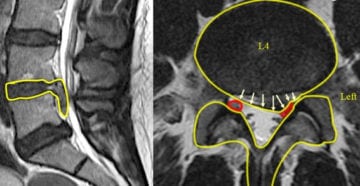

Наиболее информативны в диагностировании секвестрированных грыж МРТ и КТ. На полученных изображениях хорошо просматривается выпячивание, его локализация и размеры.

Секвестрированное грыжевое выпячивание наиболее часто образуется в поясничном отделе позвоночника. Это происходит из-за серьезных статических и динамических нагрузок, постоянно воздействующих на диски, позвонки, связки, расположенные в нижней части спины. Примерно у 50% пациентов диагностируется смещение межпозвонковых дисков (L4-L5, S1) в пояснично-крестцовом отделе. Именно они испытывают максимальные нагрузки при ходьбе, наклонах и поворотах корпуса. Грудной и шейный позвоночные отделы наименее подвержены формированию грыжи с вытеканием пульпозного ядра.